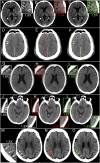

Computed tomography (CT) of the head is used worldwide to diagnose neurologic emergencies. However, expertise is required to interpret these scans, and even highly trained experts may miss subtle life-threatening findings. For head CT, a unique challenge is to identify, with perfect or near-perfect sensitivity and very high specificity, often small subtle abnormalities on a multislice cross-sectional (three-dimensional [3D]) imaging modality that is characterized by poor soft tissue contrast, low signal-to-noise using current low radiation-dose protocols, and a high incidence of artifacts. We trained a fully convolutional neural network with 4,396 head CT scans performed at the University of California at San Francisco and affiliated hospitals and compared the algorithm's performance to that of 4 American Board of Radiology (ABR) certified radiologists on an independent test set of 200 randomly selected head CT scans. Our algorithm demonstrated the highest accuracy to date for this clinical application, with a receiver operating characteristic (ROC) area under the curve (AUC) of 0.991 ± 0.006 for identification of examinations positive for acute intracranial hemorrhage, and also exceeded the performance of 2 of 4 radiologists. We demonstrate an end-to-end network that performs joint classification and segmentation with examination-level classification comparable to experts, in addition to robust localization of abnormalities, including some that are missed by radiologists, both of which are critically important elements for this application.